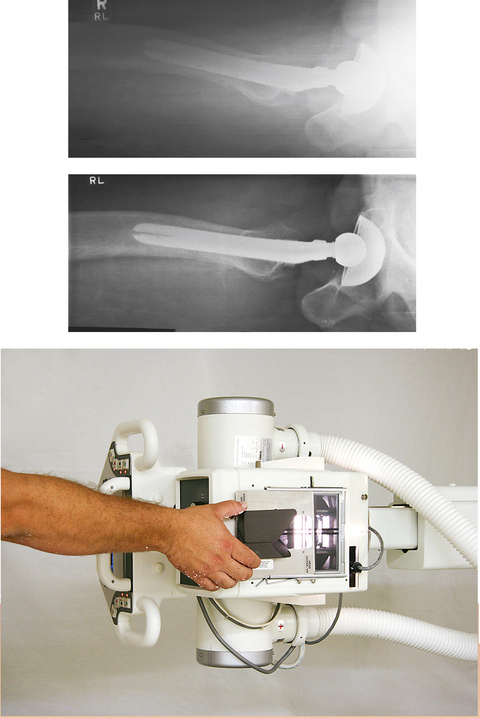

• The Ferlic swimmer’s filter is a collimator-mounted filter created to improve imaging of the lateral projection of the cervicothoracic region (swimmer’s technique) (Fig. 2-8), but it is also used for the axiolateral projection of the hip (Danelius-Miller method) (Fig. 2-9). The Ferlic shoulder filter, also a collimator-mounted filter, is designed specifically to image the shoulder in both the supine and upright positions.

Fig. 2-9 A, Axiolateral projection of hip (Danelius-Miller method) without compensating filter. B, Same projection with Ferlic swimmer’s filter. Note how acetabulum and end of metal shaft are seen on one image.